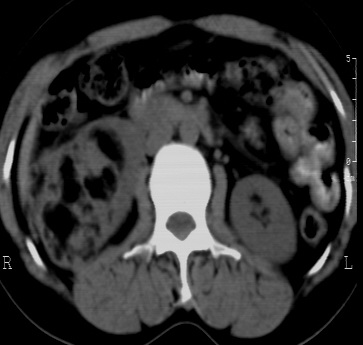

标题: CT24780:女 41岁 右肾多发低密度占位性病灶 [打印本页]

女 41岁 超声检查:右肾多发实质性包块,性质待查(提示:错构瘤或其它病变),临床病史不详。